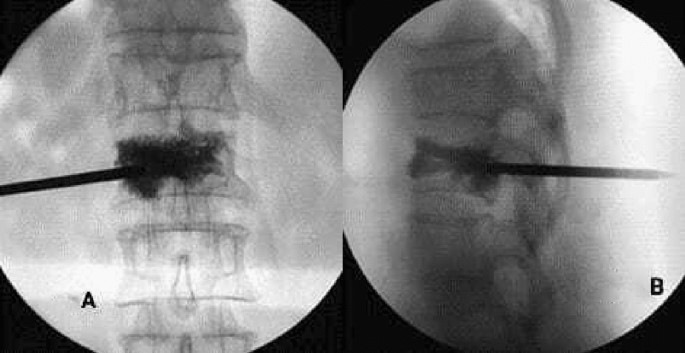

Bone cement injection volume

In the mesh optimization group, the bone cement was fully diffused into the vertebral body (Fig. 3), of which the injection volume was (5.3 ± 2.1) ml; In the traditional PVP group, the bone cement was diffused into the puncture site, but the opposite side was not fully diffused (Fig. 3), of which the injection volume was (4.4 ± 1.5) ml. There was a significant difference in the amount of bone cement injected between the two groups (t = 1.738, P = 0.048). The amount of bone cement injected in the mesh optimization group was higher by 20.5% than in the traditional PVP group.

(A) X-ray showing that the bone cement was diffused into the puncture site in the traditional PVP group, (B) X-ray showing the contralateral side was not fully diffused.

Bone cement leakage rate

There were 4 cases of bone cement penetration in the mesh optimization group (3.9%) and 20 cases in the traditional PVP group (21.9%). There was a significant difference in the incidence of bone cement penetration between the two groups (χ2 = 12.701, P < 0.001). The penetration incidence of bone cement in the traditional PVP group was about 5.5 times higher than in the mesh optimization group.